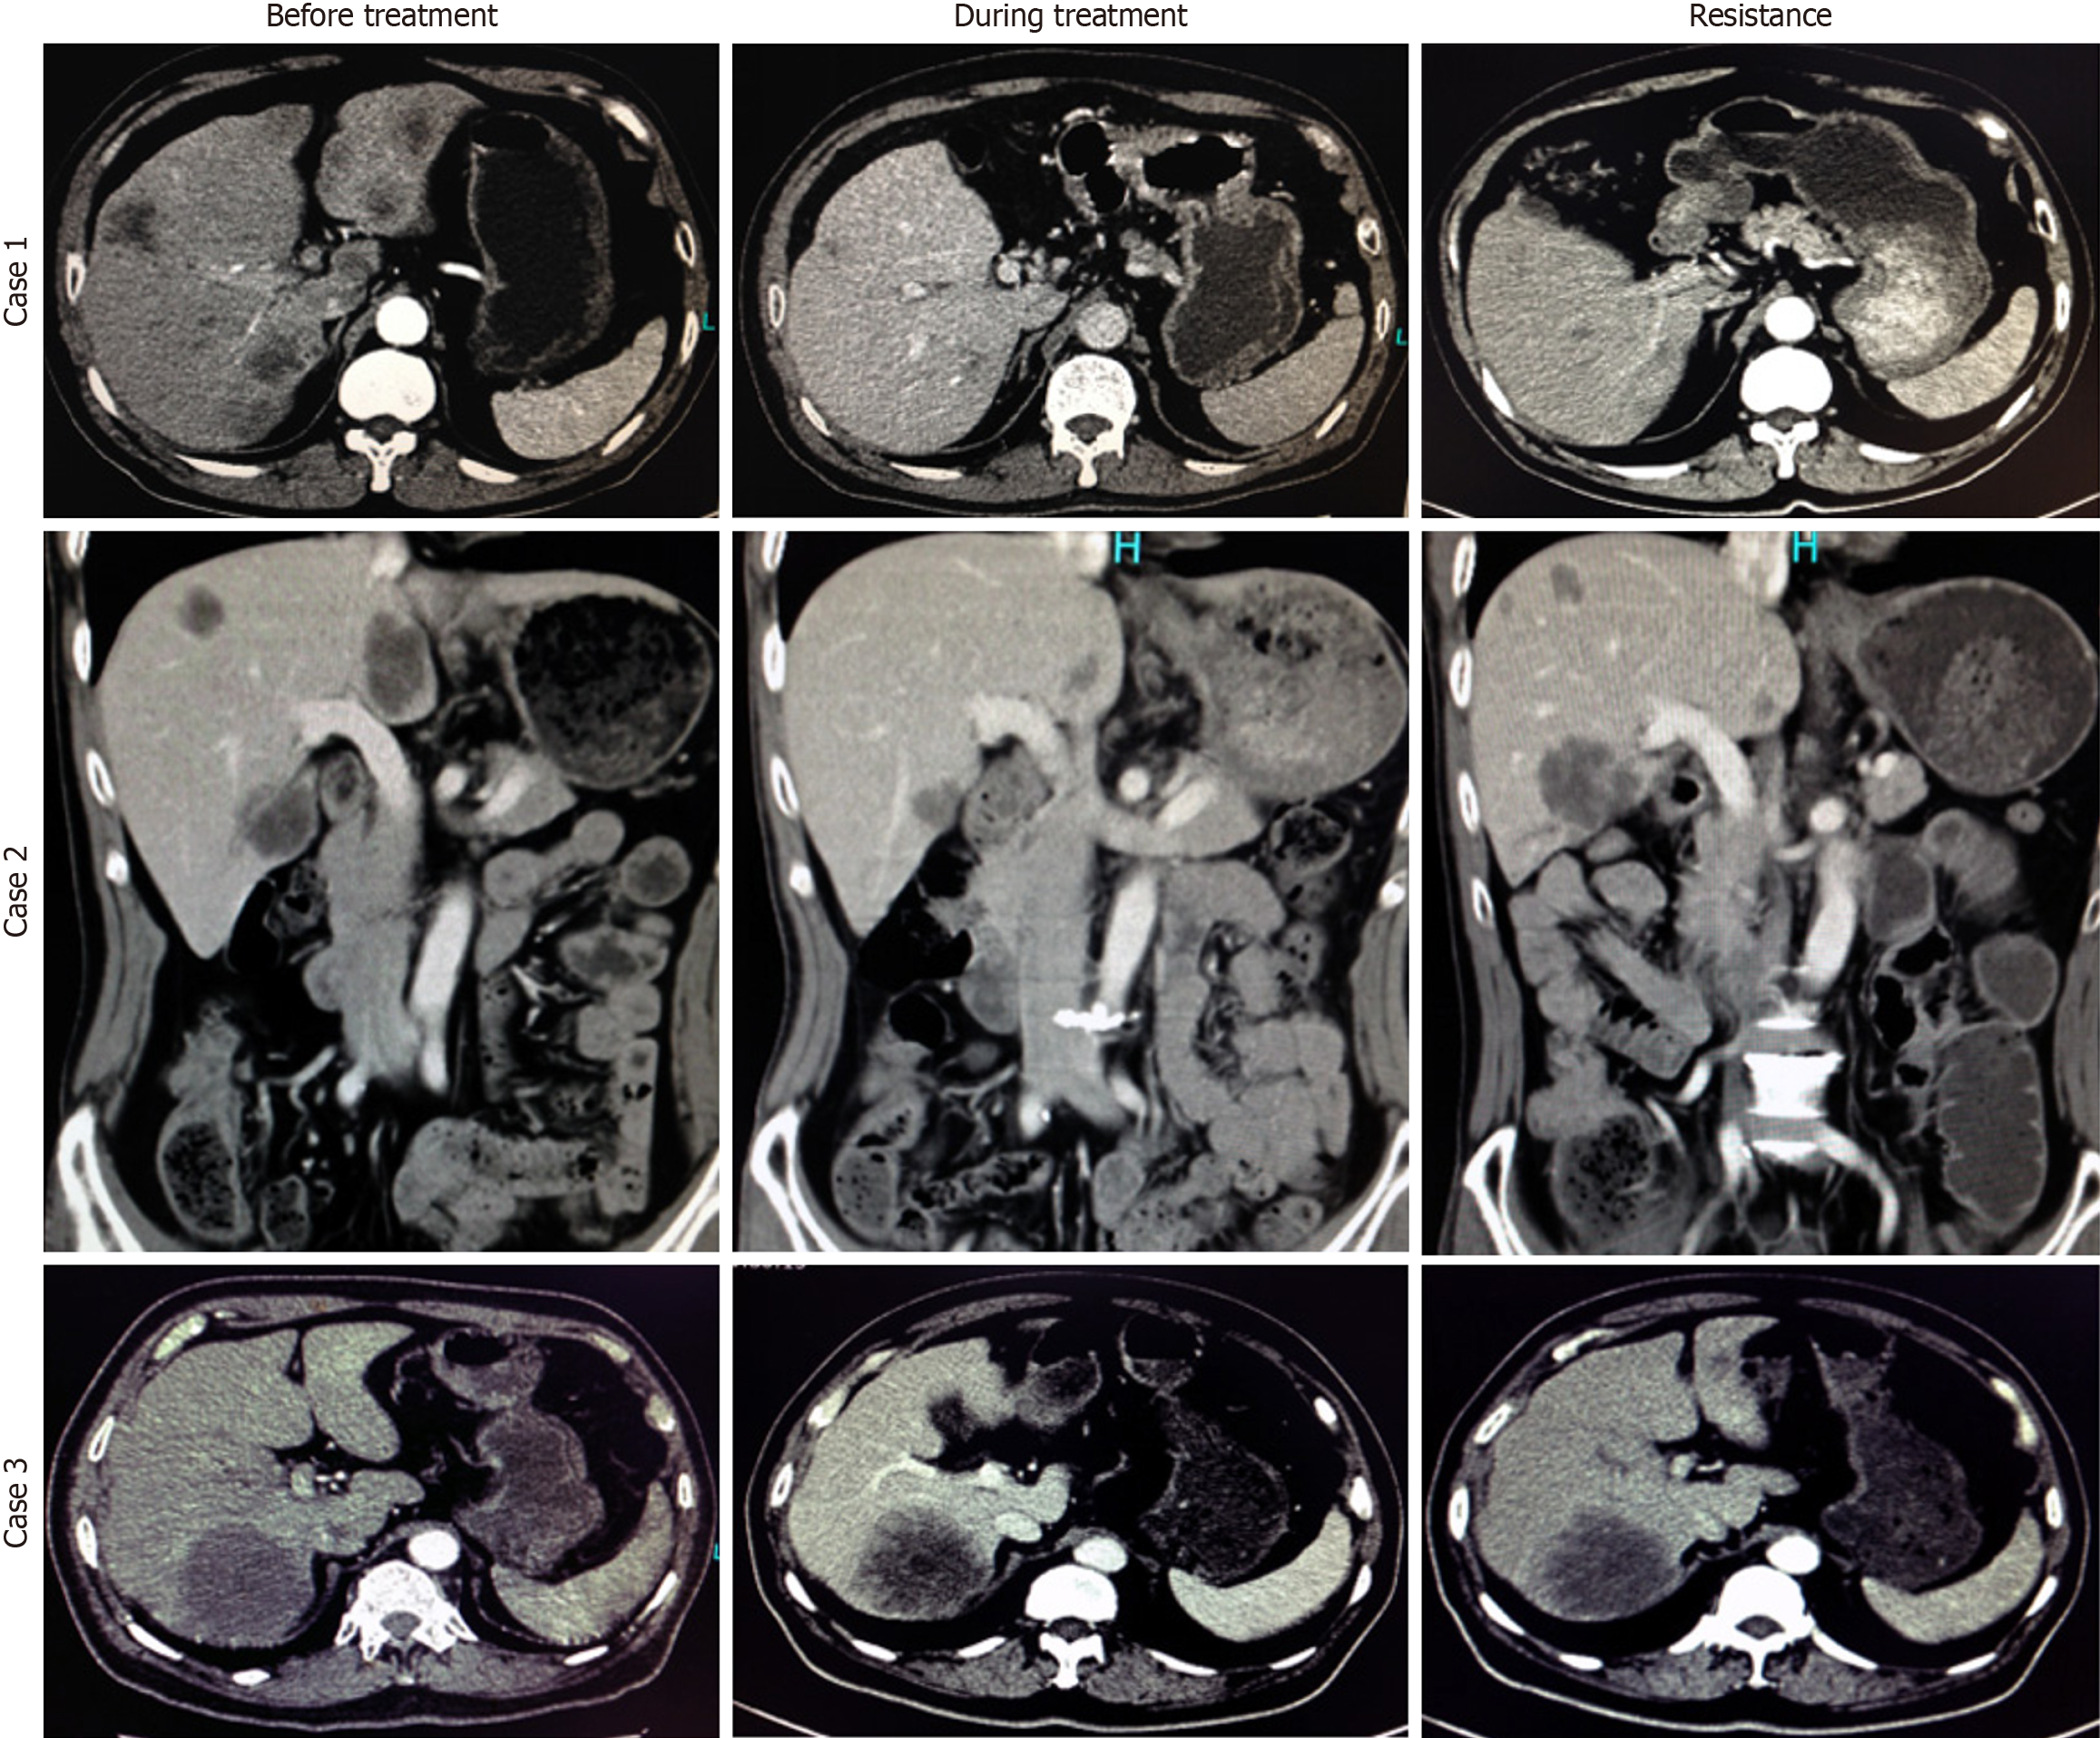

Computed tomography images of tumor size changes in three cases across different stages.

A: Case 1; B: Case 2; C: Case 3.